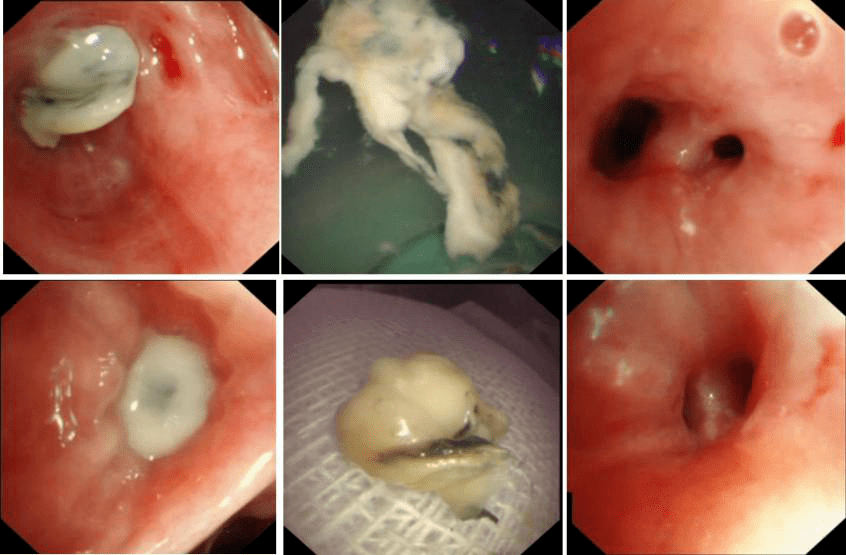

确定断后 , 给予两性霉素B静脉滴注(50mg 泊沙康唑(5ml 每日四次)抗真菌治疗 。 同时 , 于气管镜下多部位精准局部灌注两性霉素B治疗(10+15mg 每周一次) 。 并多次应用冷冻等介入方法清除支气管内脓栓(支气管管型 , 图3) 。

文章图片

图3应用冷冻等支气管镜介入技术取出脓栓 , 并应用两性霉素B进行局部灌注治疗